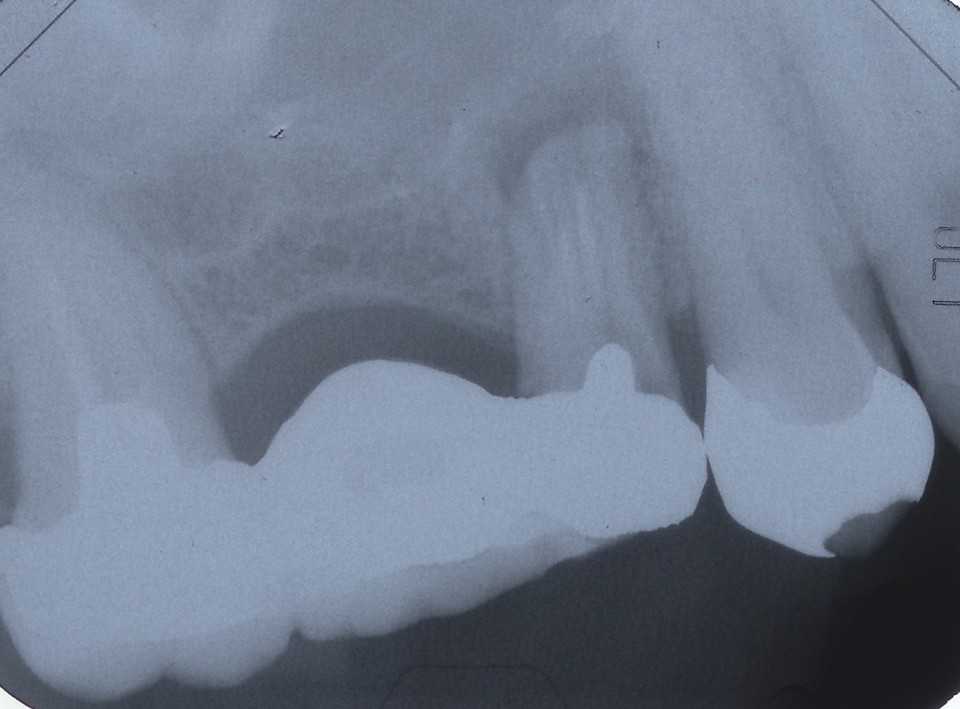

50代女性、左上5-7ブリッジ脱離、7番2次カリエス+Per(根尖性歯周炎)、強度の外傷性咬合この方、ひどい食いしばりで歯が壊れてしまう。噛み合わせの左下7番も歯冠が崩壊しつつある。7番はブリッジが脱離していて、内部は虫歯でドロドロ。Perつまり根管充填が緊密ではなく、歯根内部は細菌だらけで根の周りにはひどい炎症がある。まずはレントゲン写真から。7番の歯根の周りが炎症で黒くなっているのが分かると思う。ブリッジを全部外すと咬合が狂うので、とりあえず7番だけカットして内部を見てみた。根管充填材が見えるところまで軟化象牙質を除去して、3MIX+α-TCPを入れて根管内部を殺菌することにした。根管充填材の周りは黒くなっているのが見えると思うが、これは硫酸塩還元細菌の代謝産物の硫化鉄:FeSで、理想に反して根管充填材はゆるゆるの緊密充填ではないことを示している。このような状況は普通のことだ。歯根内部は細菌だらけということだが、ゆるゆるだから根管充填材を全部除去する必要もない。ゆるゆるの隙間から3MIX(抗菌剤)は浸透し根管は殺菌される。外傷力を弱めるために咬合調整を繰り返している。コア部分は隙間に細菌由来の黒色物質FeSがこびりつき、真っ黒。ポンティック下も細菌のコロニーでドロドロ歯質は残っているように見えるかもしれないが、ボンディング材が効く程度に軟化象牙質(虫歯)を除去すると、残根状態になる。つまり通常治療では抜歯しかないということだ。しかもPerでグラグラの動揺度2〜3、垂直性同様有りだ。とてもこのままではブリッジの支台には使えそうもない。ピンク色の根管充填材が見えると思うが、周りは真っ黒だ。その真っ黒になった隙間から細菌は侵入するし、3MIXも浸透する。こうではない緊密な根管充填治療は垂直加圧法でしか見られない。3MIX+α-TCPCR(ダイレクトボンディング)で覆う。これでないと微小漏洩が起こり失敗する。丸い形はラウンデッド・コアと呼び、この形が咬合力を内向きに集中させ歯根を守る。ポストは歯根の外側にこじるような応力を生じるので歯根を壊してしまいやすい。補綴物が必要な時はピンレッジで維持力を得る。これはCAD/CAMでは作れないだろう。これで2〜3週間様子をみる。外傷性咬合のコントロール(ナイトガードや行動療法)をしながら。つづく